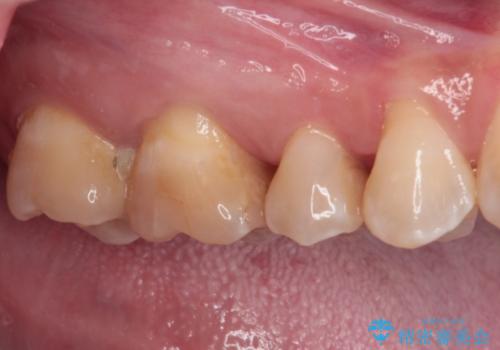

治療後は物が挟まることもなく、フロスが引っかかったり出血したりすることが減りました。